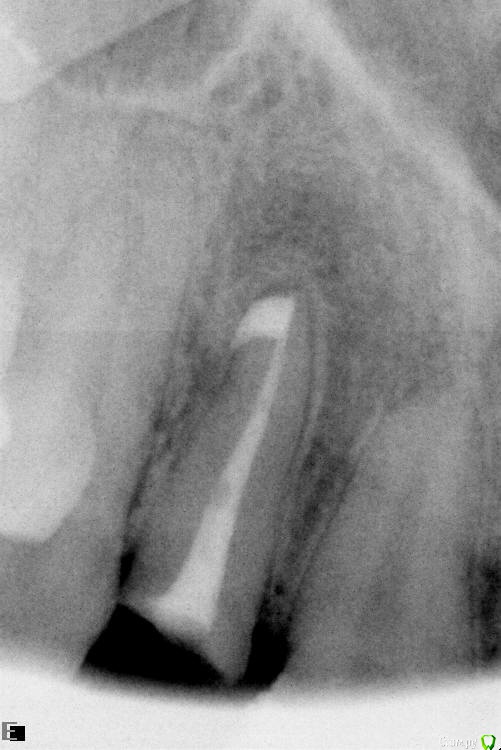

Slaggy Опубликовано 19 июля, 2016 Поделиться Опубликовано 19 июля, 2016 История -Корень 22 с выведением материала и периапикальным процессом - Удаление, кюретаж, обработка лазером, имплант+фдм и домик Нуф-Нуфа приклеенный к 21 и 23.Через 4 месяца выкрутился за формирователь. Куча грануляций, вестибулярное окно на уровне апикальной трети импланта маргинальный край кости сохранен.. Сделано -Кюретаж, Остеон2, пародонкол, ушито. Домик Нуф-Нуфа возведен вновь. По прошествии 2х месяцев -Пациент жалуется на увеличение пространства между понтиком и десной. Периодическое попадание крошек материала в полость рта. Слизистая малинового цвета. Отека нет. "Промывное пространство" увеличилось на 2 мм. В толще слизистой гранулы Остеона. Некоторые совсем у поверхности, можно ковырять зондиком..Боли или неприятных ощущение пациент не испытывает. Убирать все или подождать? Чего ждать от ситуации? Ссылка на комментарий

Slaggy Опубликовано 22 июля, 2016 Автор Поделиться Опубликовано 22 июля, 2016 Что за обработка лазером?Стерилизация лунки - Иногда лазером, иногда гексидином промываюЯ в это шаманство верю слабо, но "каждая мошка мяса - трошку" koreandrОтправлен 20 июля 2016 - 14:49Если выходит материал, значит есть откуда выходить. Дырка. Вот и вся биология. Через 2 месяца после операции дырок быть не должно в идеале. Вот и я о том - где мембран и периост? фоты нашел преоп и на момент фэйла снимок и фото Ссылка на комментарий

Slaggy Опубликовано 15 августа, 2016 Автор Поделиться Опубликовано 15 августа, 2016 (изменено) Тут просили картинки-20/05,2016 , 15/08,2016 Графт продолжает всплывать через слизистую, хрустит при пальпации области аугментации Почистил слизистую от графта, дам паузу 2 недели и вычищаю все начисто. Изменено 15 августа, 2016 пользователем Slaggy Ссылка на комментарий